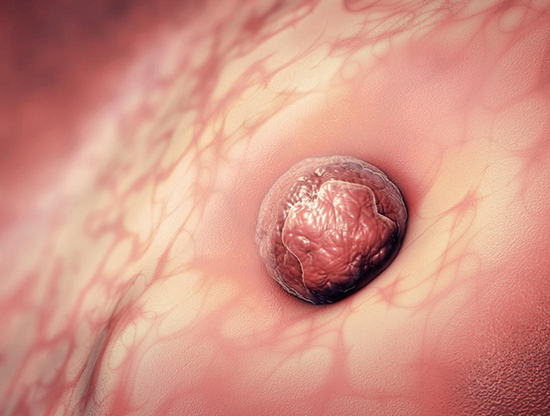

成功怀孕会经历以下几不同的阶段。- 精子必须到达并穿透并使女人的卵子受精。 - 产生的受精卵必须分裂并形成胚泡。 - 胚泡到达子宫并植入子宫内膜。 - 植入的胚泡...

试管婴儿精子和卵子结合形成受精卵,发育成胚胎,发育的胚胎需要在子宫内定居,胚胎着床需要多长时间?在卵子受精后,从输卵管到子宫需要几天的时间,胚胎继续生长和分裂,最...